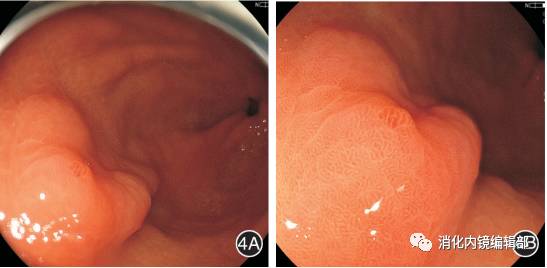

图4  病理诊断为慢性炎症的病变镜下特征4A:普通白光胃镜可见胃窦前壁近大弯侧一0.3 cm×0.3 cm大小的Ⅱa型病变;4B:白光单独放大可见病变表面微血管和微腺管结构稍不规则,边界清楚;4C:BLI-contrast放大下可见病变表面的微血管和微腺管结构稍紊乱,无异型增生血管,病变与组织周围边界不清楚;4D:BLI-bright放大下可见病变表面微腺管及微血管结构排列稍不规则,但无消失及异型增生血管,病变与周围组织边界不清楚